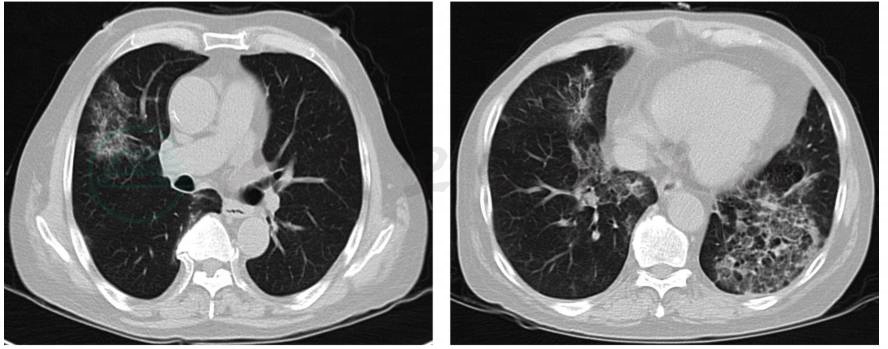

患者于2017年6月7日复查肺部CT显示:双肺多发实变影,同2017年5月4日大致相仿。肺部阴影无明显吸收(图2)。以上提示常规抗感染治疗无效,应考虑肺感染因素导致的双肺病变。为进一步明确诊断,于2017年6月9日行CT引导下经皮肺穿刺,病理提示类脂质性肺炎。

图2 胸部CT平扫:双肺多发实变影,同2017年5月4日比较病灶吸收不明显